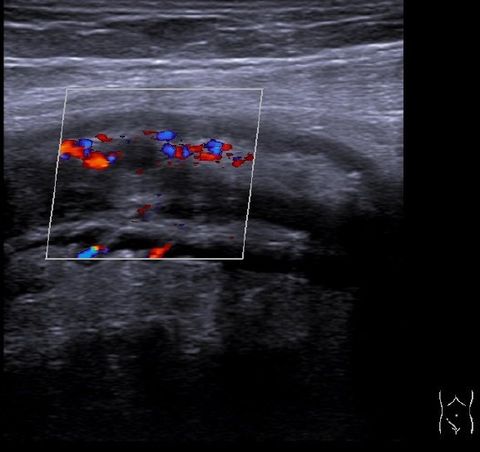

Ultraschalluntersuchungen

Von der Krebsvorsorge und -nachsorge bis zum Gallensteinleiden: Die Ultraschalluntersuchung (Sonografie) ist eine schmerzfreie Methode zur Kontrolle der inneren Organe. Dabei werden die Strukturen des Körpers durch Ultraschallwellen bildlich dargestellt.

Wir bieten folgende Ultraschalluntersuchungen an:

Abdomen (Bauchorgane wie Leber, Galle, Bauchspeicheldrüse, Nieren, Milz, Darm...) incl. der Bauchgefäße

Schilddrüse, Halsorgane

Thoraxsonographie (Brustkorb, Rippenfell)

Untersuchung auf Bauchaortenaneurysma im Rahmen der Vorsorge bei Männern ab 65 Jahren